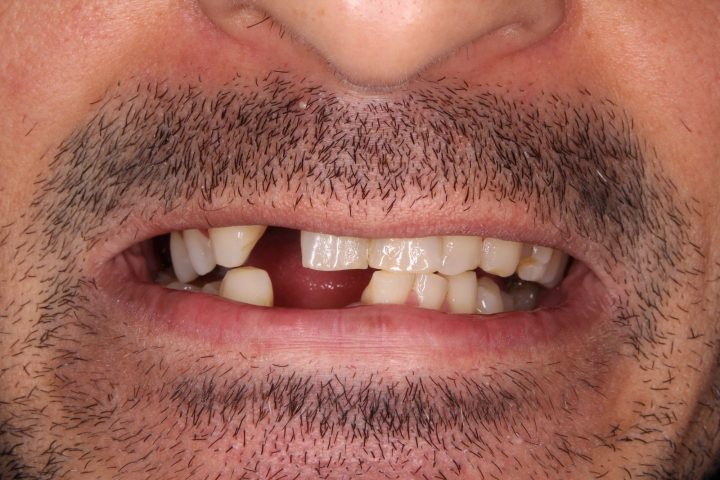

Ibrahim

Ibrahim ist einen von den französischen Patienten, wer früher sowohl oben, als auch unten herausnehmbare Zahnersatz hatte. Die Prothese hatte große Gaumenplatte, und deswegen konnte er die obere nicht tragen.

Er hatte ständig Brechreiz, und hat immer gewürgt, daneben war die Stabilität auch problematisch.

Die Prothesen haben sich ohne Klebstoff bewegt, und er hat sich aufgeregt, wenn er gesprochen hat. Er hatte davon Angst, dass die Prothese einmal ausfällt. Deswegen hat er die Klinik besucht.

Er hat oben und unten festsitzende Prothese auf Implantaten bekommen, womit er restlos zufrieden war. Diese Prothesen bewegen sich nicht weder beim Kauen, noch beim Sprechen.

Dank der Prothese, die keine Gaumenplatte hat, kann er sorglos den Zahnersatz tragen.